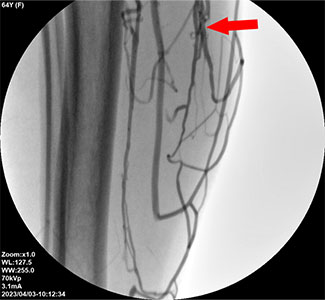

下肢静脈瘤の再発の原因は、細静脈の検査と閉塞の未実施下肢静脈瘤の再発の原因は明らかです。そのため、まずは原因を特定することが重要です。下肢静脈瘤の再発には、主に2つの原因があります。

問題がなかった静脈に新たな問題が発生する場合と、以前治療した血管に症状が再発する場合です。

特に、治療した血管に問題が再発する場合は、患部の血管を完全に閉塞できていなかったために逆流が生じて起こったと思われます。

これには患部の血管を取り囲む細静脈の微細な逆流を見逃したケースも含まれます。

すなわち、これらの細静脈を完全に閉塞できなかったことが再発の主な原因といえます。